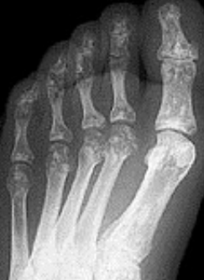

| Describe the alignment of metatarsal 2 | There is no angulation nor displacement of the distal segment relative to the proximal segment. |

| Describe the alignment of metatarsal 3 | The distal segment is displaced laterally (50% apposition) and angulated medially. |

| Describe the alignment of metatarsal 4 | The distal segment is displaced laterally (75% apposition) but there is no apparent angulation. |

| Describe the tubulation of the metatarsals | Metatarsals are overtubulated - decreased girth. |

| Describe the tubulation of the metatarsals | Metatarsals are undertubulated - increased girth. |